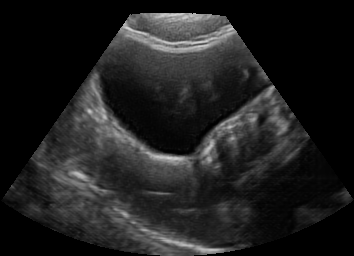

Real in-vivo images. 22 ultrasound sequences were collected using a GE Voluson E8 machine during standard fetal screening exams of 8 patients. Each sequence is several seconds long. We extracted all 4427 frames and resize them to , see Fig. 2 for some examples. The resulting image set was randomly split into training-validation-test sets by a 80-10-10% ratio.